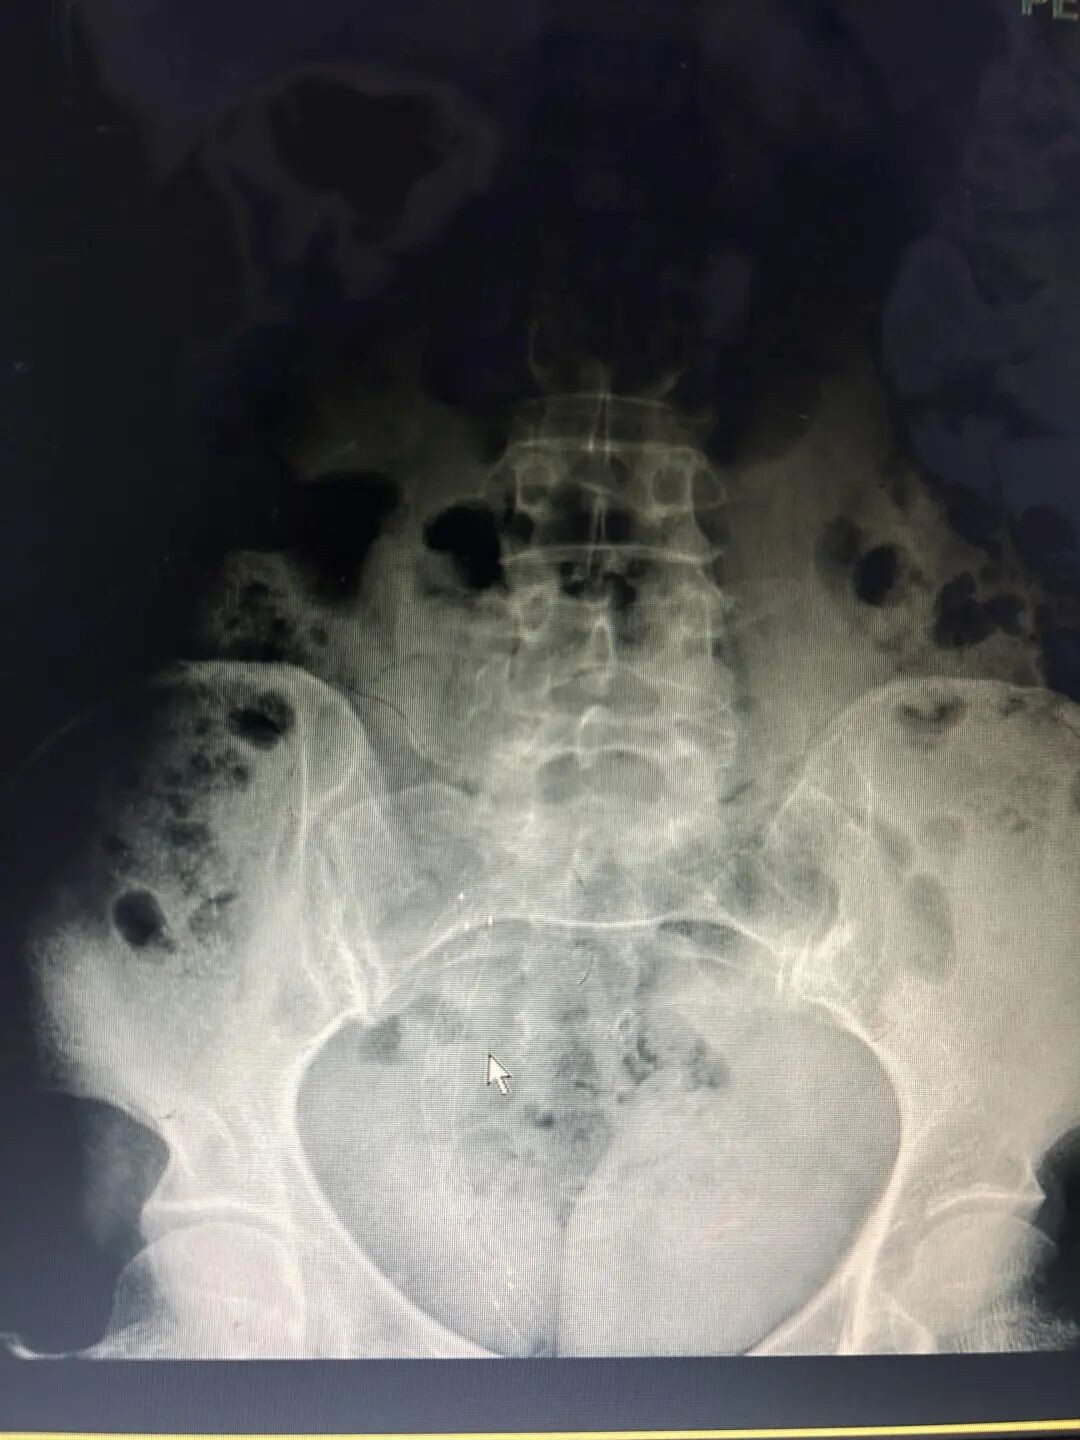

图为术后复查尿路平片,覆膜支架扩张良好,位置正常